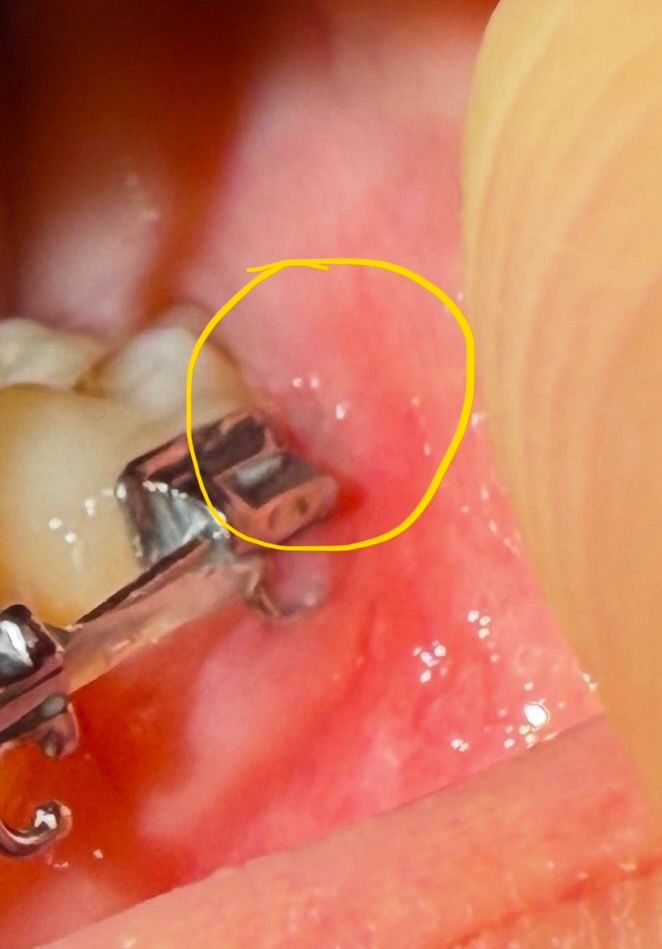

사진 첨부합니다. 보시고 답변해주세요ㅠ

와이어 길이 자른다구 잘라주신 것 같아요

근데 철사가 입안 살에 좀 박혀있었는데

자르면서 입안에 상처가 나서 좀 살이 잘려나갔더라구요

근데 그 안에 철사가루?? 같은게 다 껴있는데

면봉으로 살살 문질러도 다 빼내긴 역부족이었어요ㅠ

근데 이상태로 살이 차올랐는데 ㅜ 괜찮나요..?

사진은 살 차오르기 전, 후입니다